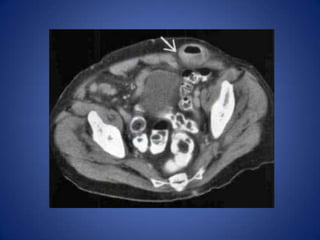

Pseudomembranous or Infectious

Colitis

• Usually diffuse, pancolonic with impressive

colonic wall thickening ("accordion sign")

• May be segmental, including distal colon

• Very common, especially in hospitalized

patients, and those in nursing homes

Pseudomembranous or Infectious Colitis •Usually diffuse, pancolonic with impressive colonic wall thickening ("accordion sign") • May be segmental, including distal colon • Very common, especially in hospitalized patients, and those in nursing homes